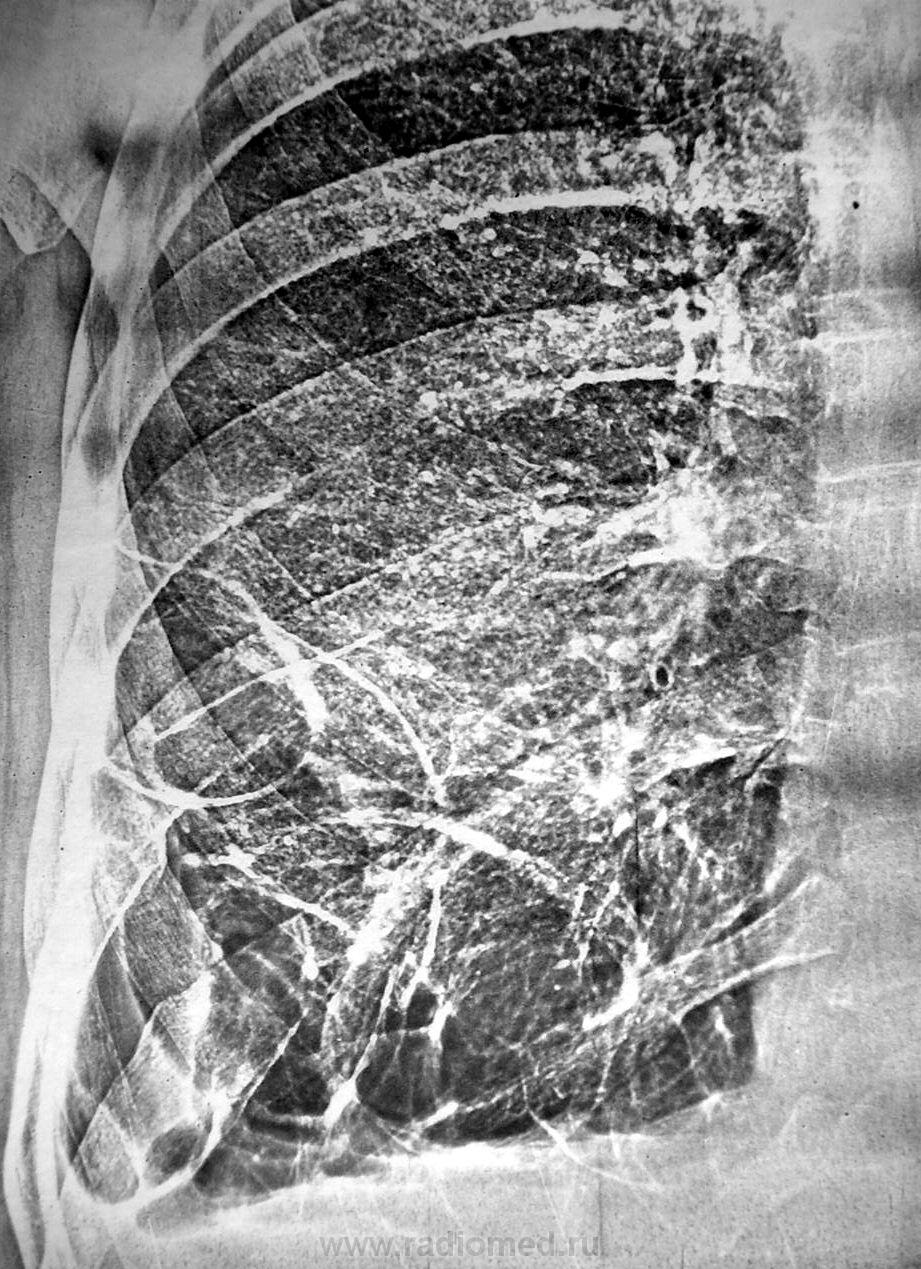

Год назад появились локальные изменени внизу справа.

Поликистоз нижней доли правого лёгкого.

Можно спороть хохму - назвать и "буллёз".

Однако, буллы логичнее.

Частичная облитерация синусов, конечно, несколько смущает.

Хотя, с учетом наличия консолидированных переломов справа, возможна и другая версия.

Но обычно такие буллы развиваются в верхних отделах легких, а в этом случае локально внизу. Возможно правильно подумать и о связи с травмой - но нет архива...

Может, остаточные плевральные полости? Без линейной томографии не определить, в плевральной полости или в субплевральных отделах. Для исключения диафрагмальной грыжи можно было контрастировать ЖКТ. Но раз архив, буду с нетерпением ждать верного ответа

Травма - перелом ребер + ушиб легкого - гемоторакс + пневмония - обратное развитие - пневмосклероз + плевральные наслоения - облитерация мелких бронхов - клапанная обструкция мелких бронхов - псевдокисты (буллы). Таких схем можно придумать множество. Без анамнеза - пустое дело.

Выскажу простую гипотезу, может быть кто-то разовьёт. Поскольку в образовании булл имеет значение клапанный механизм, можно предположить, что год назад он появился. Например эндобронхиальная опухоль в бронхе базальной пирамиды. Боковая проекция вроде бы подтверждает такое предположение.